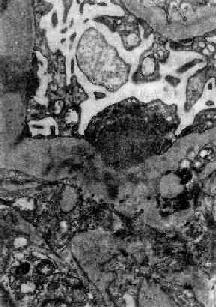

图12-7 弥漫性毛细血管内增生性肾小球肾炎 肾小球内细胞数量增多,系膜细胞和内皮细胞增生并有少量中性白细胞浸润,毛血管腔狭窄 上皮细胞一般无明显增生,少数严重的病例肾小球的壁层和脏层上皮细胞可增生,形成新月体。这种病变容易引起肾小球纤维化。如数量少,对功能影响不大。如病变广泛,可发展为新月体性肾炎。 在电子显微镜下可见肾小球系膜细胞和内皮细胞增生肿胀。基底膜和脏层上皮细胞间有致密物质沉积。这些沉积物大小不等,有的很大,在基底膜表面呈驼峰状或小丘状(图12-8,图12-9)。沉积物表面的上皮细胞足突多消失。基底膜变化不明显有时边缘稍不规则。沉积物一般在发病后几天就可出现,在4~6周内消失。有时基底膜内侧内皮细胞下和系膜内也可见小型沉积物。

图12-8 毛细血管内增生性肾小球肾炎 电镜下见肾小球毛细血管基底膜表面上皮细胞下有多数驼峰状电子致密沉积物

图12-9 毛细血管内增生性肾小球肾炎 电镜下见驼峰状沉积物位于毛细血管基底膜表面。沉积物表面有上皮细胞覆盖,上皮细胞足突消失 免疫荧光法检查显示,在肾小球毛细血管壁表面有免疫球蛋白和补体沉积(主要为IgG和C3),呈颗粒状荧光。系膜内也可有类似沉积物。 肾小球的病变可引起相应的肾小管缺血,肾小管上皮细胞常有浊肿、玻璃样变和脂肪变等。管腔内含有从肾小球滤过的蛋白、红细胞、白细胞和脱落上皮细胞。这些物质在肾小管内凝集,形成各种管型,如蛋白管型、透明管型、细胞管型(如红细胞、白细胞或上皮细胞管型)、颗粒管型。 肾间质内常有不同程度的充血、水肿和少量淋巴细胞、中性粒细胞浸润。 肉眼观,早期变化不明显。以后肾轻度或中度肿大、充血、包膜紧张、表面光滑、色较红,故称大红肾。若肾小球毛细血管破裂出血,肾表面及切面可见散在的小出血点如蚤咬状,称蚤咬肾。切面可见皮质由于炎性水肿而增宽,条纹模糊与髓质分界明显。 【临床病理联系】 这种肾炎的主要临床症状为尿的变化,水肿和高血压。 1.尿的变化由于肾小球毛细血管损伤,通透性增加,故常有血尿、蛋白尿、管型尿等。 (1)血尿:血尿常可反映肾小球毛细血管损伤的情况。轻度血尿需用显微镜才能发现。严重的血尿,肉眼可见尿呈鲜红色。有时尿中红细胞溶解,血红蛋白在酸性尿中转变成酸性血红素,使尿呈棕红色。 (2)蛋白尿:蛋白尿的程度不同,一般不很严重,但少数病人尿中可有大量蛋白质。 (3)管型尿:在肾小管内凝集形成的管型随尿液排出,尿液内可出现各种管型,称为管型尿。 (4)少尿:由于肾小球细胞增生肿胀,压迫毛细血管,致管腔狭小,肾血流受阻,肾小球滤过率降低,而肾小管再吸收无明显障碍,可引起少尿,致水钠在体内潴留。严重者并可有含氮代谢产物潴留,引起氮质血症。 2.水肿病人常有轻度或中度水肿,往往首先出现在级织疏松的部位如眼睑。水肿的原因主要是由于肾小球滤过减少,而肾小管再吸收功能相对正常,引起水钠潴留。此外,也可能与变态反应所引起的全身毛细血管痉挛和通透性增加有关。 3.高血压病人常有轻至中度高血压。过去认为这种肾炎时的高血压与肾小球毛细血管阻塞,肾组织缺血引起肾素分泌增加有关。但病人血中肾素浓度多在正常范围之内。因此高血压的主要原因可能与水钠潴留引起的血量增加有关。严重的高血压可导致心力衰竭及高血压性脑病。 【结局】 这种肾炎的预后与年龄和病因有一定关系。儿童链球菌感染后肾小球肾炎的预后很好,95%以上可在数周或数月内症状消失,病变消退,完全恢复。少数病人病变消退较慢,肾小球系膜增生,可持续数月甚至1~2年。临床上,病人常有迁延性蛋白尿和复发性血尿。有时无明显症状,成为隐匿性肾炎。这种病变大多以后仍可消退,恢复正常。少数病人(约占1%~2%)临床症状消失,但病变持续不退,以后症状可反复,逐渐发展为慢性硬化性肾小球肾炎。极少数病人病变严重,发展较快,同时有明显的肾球囊上皮细胞增生,形成大量新月体,可发展为新月体性肾小球肾炎。这些病人常迅速发生急性肾功能衰竭,预后差。还有极少数(<1%)病人病变严重,发展迅速,在短期内发生肾功能衰竭、心力衰竭或高血压性脑病。 一般成人患感染后肾小球肾炎者预后较差,发生肾功能衰竭和转变为慢性肾炎者较多。此外,由其他感染引起的肾炎转变为慢性肾小球肾炎者,比链球菌感染后肾炎转为慢性者多见,预后也较差。